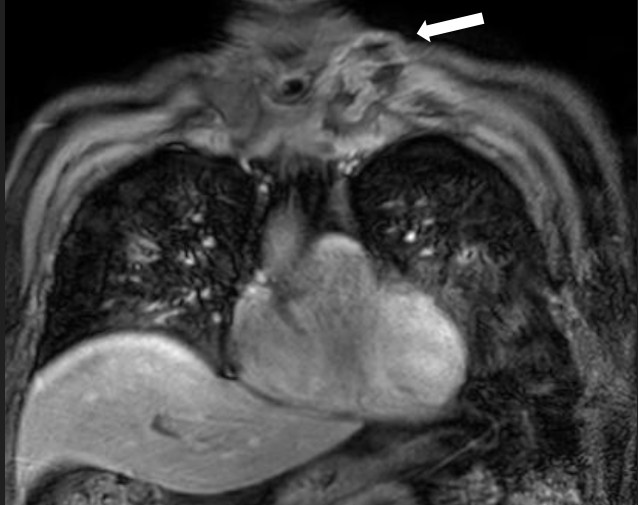

MRI of the chest showed findings consistent with osteomyelitis, including bone irregularities, edema, subchondral erosions of the right sternoclavicular joint, synovitis, and inflammatory joint changes (Fig. 2- 4).

Figure 2. Sagittal magnetic resonance imaging (POS-DIXON) (Multi-Dixon). Lytic lesion with ill-defined contour and soft tissue edema (stenoclavicular)

Figure 4. Coronal magnetic resonance imaging ESAG T2. Osteolytic lesion in sternal profile with periosteal reaction of the manubrio.